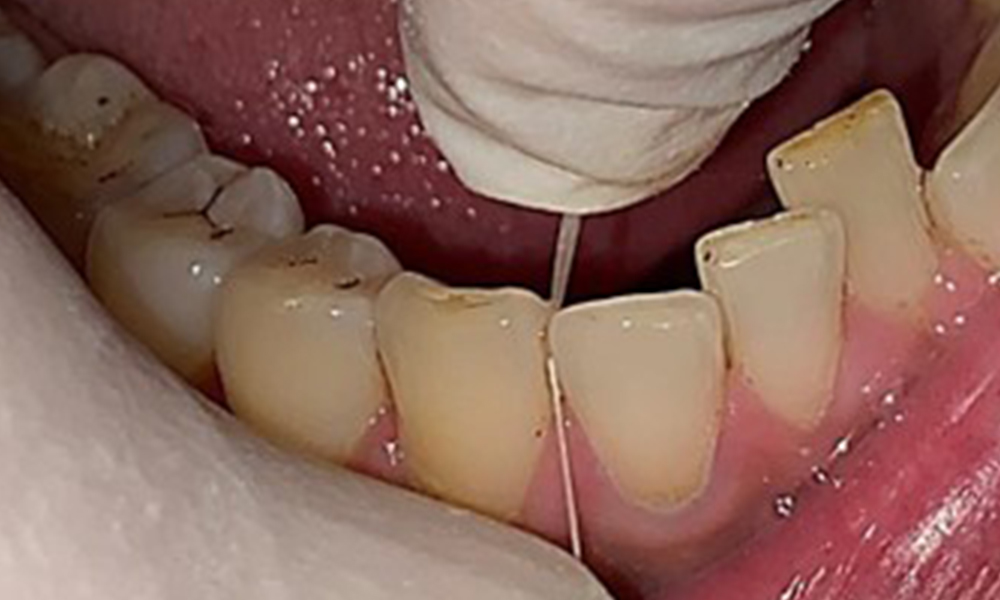

The patient has full dentition with a total of 28 teeth. There were noteworthy erosions and attritions. (Fig. 4, Fig. 5). Due to bruxism, the patient has been wearing a splint with an adjusted bite block at night for many years. The erosions were caused by long-term consumption of isotonic beverages. No periodontal bone loss or active caries were observed.

Full complement of adult teeth with no caries or radiologically recognizable bone loss was observed (Fig. 6). Radiological enamel and cusp loss were particularly evident on 36 and 37.